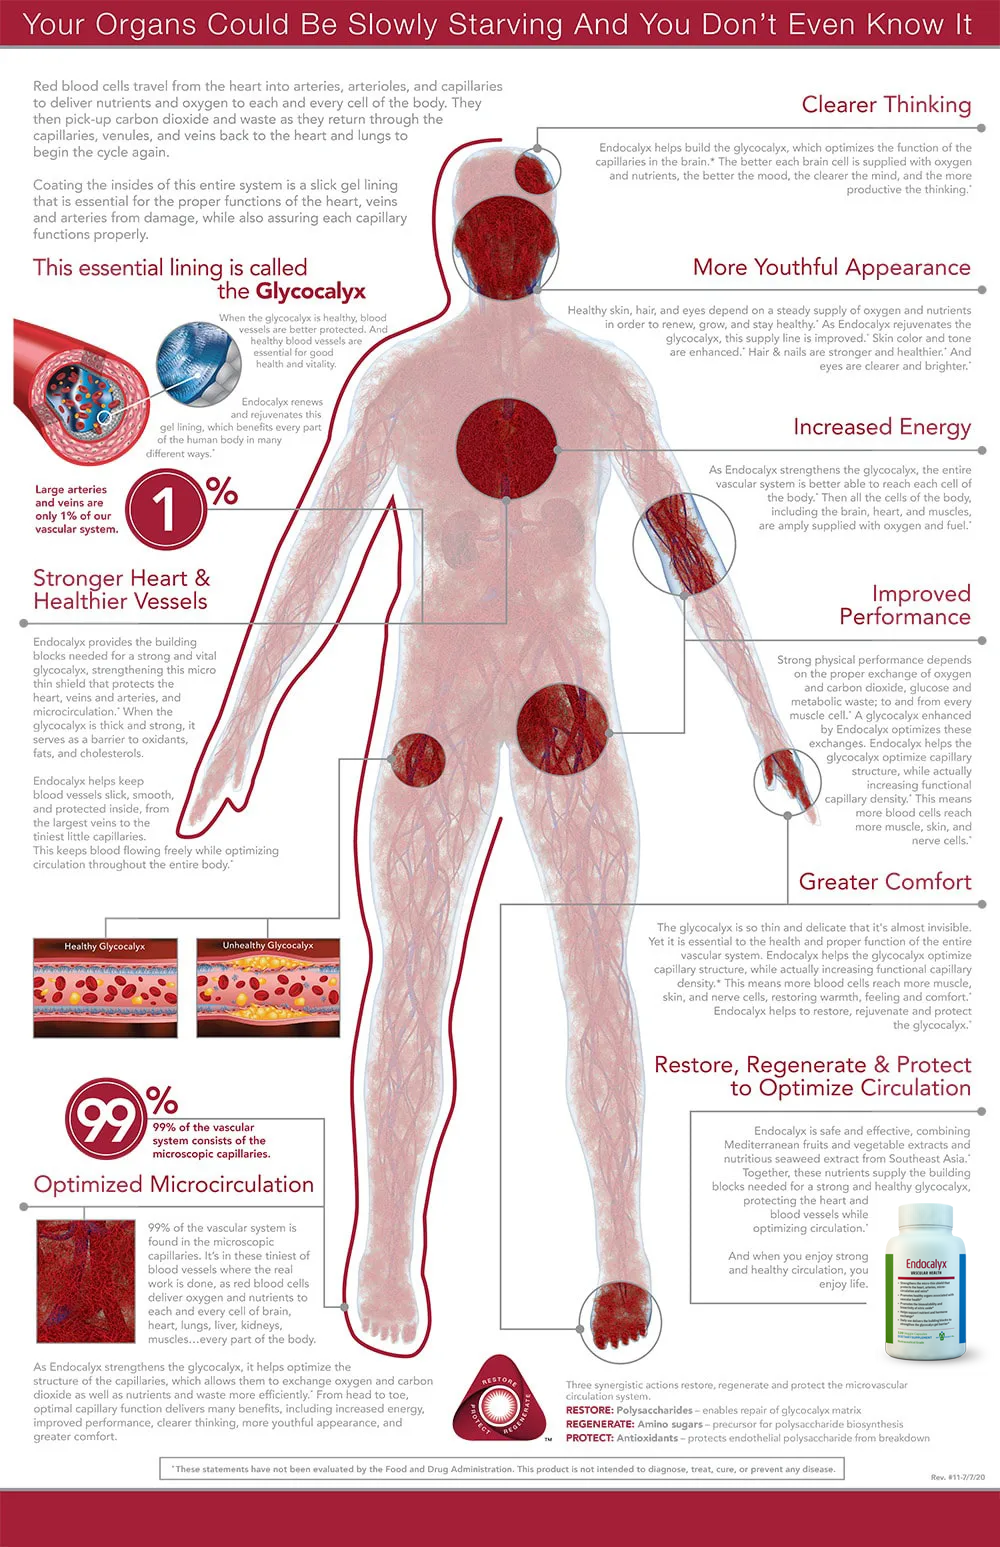

Endocalyx Anti-Aging Supplement

Endocalyx™ is the only proprietary, patented anti-aging supplement that has been clinically shown to maintain a healthy glycocalyx.*

The glycocalyx is the micro-thin gel layer that lines the inside of all blood vessels throughout the body and all organs.

Endocalyx provides the anti-aging building blocks needed for a strong and vital glycocalyx, strengthening this micro-thin shield that protects the heart, arteries, microcirculation and veins.* It helps keep blood vessels slick, smooth and protected inside, from the largest arteries and veins to the tiniest capillaries.* This keeps blood flowing freely while optimizing circulation throughout the entire body.*

Endocalyx strengthens the glycocalyx and helps optimize the structure of the capillaries, which allows them to exchange oxygen and carbon dioxide, nutrients and waste more efficiently.*

Aging, diet, disease, lack of exercise, genetics, stress and smoking can cause the glycocalyx to become compromised.*

Endocalyx promotes healthy organs associated with vascular health, including the heart, brain, kidneys, lung, muscle, skin and eyes.*

When the glycocalyx is thick and strong, it serves as a barrier to oxidants, fats and cholesterol.*

Patented Formulation with Three Classes of Compounds

Restorative Properties of Polysaccharides: Endocalyx is made with a brown seaweed called Laminaria Japonica. An extract is produced that is certified to have a minimum extract rate of 85% of the compound fucoidan sulfate. Fucoidan sulfate is validated as a hybrid of heparan sulfate and chondroitin sulfate and has a high binding affinity for heparanase. The fucoidan repairs the glycocalyx and prevents breakdown by inhibiting the heparanase activity. In addition to the fucoidan sulfate, Endocalyx also contains high molecular weight hyaluronan which is essential to provide the glycocalyx with its structural stability and dimension.

Regenerative Properties of Amino Sugars: A high dose of glucosamine sulfate, 1,500 mg (vegetarian) provides the building blocks for glycocalyx synthesis. Research confirms that glucosamine at this concentration boosts endothelial cell glycocalyx production.

Protective Properties of Antioxidants: Microvascular Health Solutions developed a next-generation proprietary blend of polyphenol and flavonoids consisting of the most efficacious fruits and vegetables clinically shown to produce anti-oxidant activity. Olive (fruit) extract, artichoke (leaf) extract, red and white grapes (fruit) extract. We increased the amounts of these ingredients to provide evidence based effective doses. We added superoxide dismutase (from bitter melon concentrate). We also added catalase (also from bitter melon concentrate). It is also verified that these antioxidant ingredients survive oral intake and arrive in the vascular compartment at clinically effective dosages.

Patents: Filed and Granted as a Method of Treatment for the Endothelial Glycocalyx based on the synergistic action of three classes of compounds. This patented anti-aging supplement formula has been clinically shown to improve the health of the glycocalyx using seven synergistic ingredients from three classes of compounds:

RESTORE: Polysaccharides – enables repair of glycocalyx matrix (fucoidan sulfate and HMW hylaronan)

REGENERATE: Amino sugars – precursor for polysaccharide biosynthesis (veggie glucosamine)

PROTECT: Antioxidants – protects endothelial polysaccharide from breakdown (polyphenol, flavonoids, SOD, catalase, heparanase inhibitor).